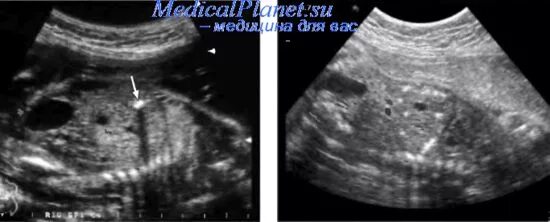

Гиперэхогенные структуры на узи. мелкие гиперэхогенные структуры в почках на узи. гиперэхогенная структура паренхимы печени. гиперэхогенные включения в печени на узи.Гиперэхогенные образования в печени на узи.Доброкачественные опухоли печени на узи. гиперэхогенные образования в печени на узи. гиперэхогенные включения в печени на узи.Узи селезенки гиперэхогенные образования. гиперэхогенное образование в печени. гиперэхогенные образования в печени на узи. гиперэхогенные структуры на узи.Гиперэхогенные включения в печени на узи. узи селезенки гиперэхогенные образования. гиперэхогенное образование в селезенке.Гиперэхогенное включение в печениГиперэхогенное образование в печени на узи что это такое. газ в портальной системе печени на узи. гиперэхогенные включения в печени на узи. гиперэхогенные точечные включения в селезенке на узи.Гиперэхогенная печень. гиперэхогенные образования в печени. гиперэхогенная печень на узи. гиперэхогенное образование в печени на узи что это такое.Гиперэхогенные включения в печени на узи. холангит на узи.Узи анатомия почек. гиперэхогенные линейные структуры. точечные гиперэхогенные включения в печени. гиперэхогенные включения в миометрии.Гиперэхогенное включение в печениТочечные гиперэхогенные включения в печени. гиперэхогенное образование в почке что это. симптом гиперэхогенных пирамид в почках на узи. гиперэхогенные тяжи на узи.Гиперэхогенные структуры на узи. гиперэхогенные включения без акустической тени. узи селезенки гиперэхогенные образования. гиперэхогенное образование в печени на узи что это такое.Гиперэхогенные включения в печени на узи. амебный абсцесс печени на узи. гиперэхогенный очаг в печени. неоднородное образование в печени на узи.Метастатическое поражение печени узи. образования печени на узи. гиперэхогенные образования.Гиперэхогенное включение в печениГиперэхогенные образования. гиперэхогенное образование на узи. гиперэхогенные образования в печени.Метастазы в печень гиперэхогенные узи. гиперэхогенное образование. гиперэхогенные включения. множественные гиперэхогенные включения в печени.Гиперэхогенные включения поджелудочной железы. гиперэхогенные включения в печени на узи. узи множественные гиперэхогенные. кальцинаты в простате на узи.Подкапсульная гематома печени на узи. гиперэхогенные образования в печени. гиперэхогенные включения в печени. гиперэхогенное образование в печени по узи.Гиперэхогенные образования в печени на узи. гепатоцеллюлярная аденома печени узи. гиперэхогенный очаг в печени на узи. очаговый липоматоз печени узи.Гиперэхогенные образования. множественные гиперэхогенные образования. гиперэхогенные образования в печени. образование брюшной полости узи.Гиперэхогенное включение в печениГиперэхогенная печень. гиперэхогенный желчный пузырь. гиперэхогенное образование в желчном пузыре. гиперэхогенные образования в печени.Узи желчного пузыря гиперэхогенные. гиперэхогенный желчный пузырь узи. гипоэхогенное образование в желчном пузыре. гиперэхогенное образование в желчном пузыре.Гиперэхогенное включение в печениГиперэхогенный полип эндометрия. гиперэхогенное. множественные гиперэхогенные образования.Гиперэхогенное включение в печениГиперэхогенные образования в печени на узи. гипоэхогенные образования в печени метастазы. гипоэхогенное образование при узи печени.Гиперэхогенное включение в печениГиперэхогенное неоднородное образование в печени. гиперэхогенные структуры. в полости матки гиперэхогенное образование. гиперэхогенные линейные структуры.Гиперэхогенные включения в печени на узи. гиперэхогенный очаг в мочевом пузыре.Гиперэхогенные участки на узи. гиперэхогенное включение. гиперэхогенные включения в яичнике.Гиперэхогенное включение в печениКонкремент в мочевом пузыре узи протокол. линейное гиперэхогенное образование. гиперэхогенное образование на узи.Синдром гиперэхогенных пирамид почек узи. узи селезенки гиперэхогенные образования. гиперэхогенные включения в печени на узи. образование почки на узи в паренхиме.Гиперэхогенное образование на узи. узи анатомия почек. точечные гиперэхогенные включения в печени.Сонограмма поджелудочной железы. кольцевидная поджелудочная железа узи. гиперэхогенное образование поджелудочной железы узи. гиперэхогенные включения в печени на узи.Гиперэхогенная структура на узи. гиперэхогенное образование на узи. гиперэхогенное образование диаметром 21 мм. гиперэхогенные включения до 3-4 мм.Гиперэхогенные включения. гиперэхогенные включения в матке. гиперэхогенное точечное включение. гиперэхогенные включения в цервикальном канале.